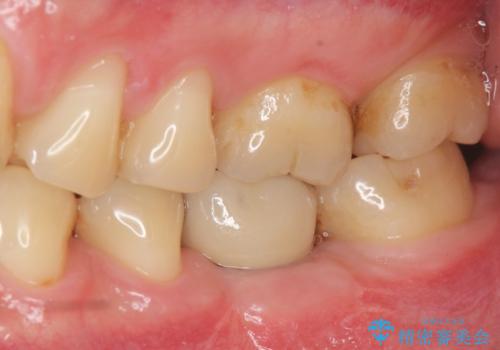

- 44万円(インプラント・チタンカスタムアバットメント・ジルコニアクラウン・仮歯)費用は治療当時の料金となります

抜歯後、骨の再生を待ったことで、清掃性の高い位置に埋入を行い機能的・審美的なインプラント治療を行うことができました。